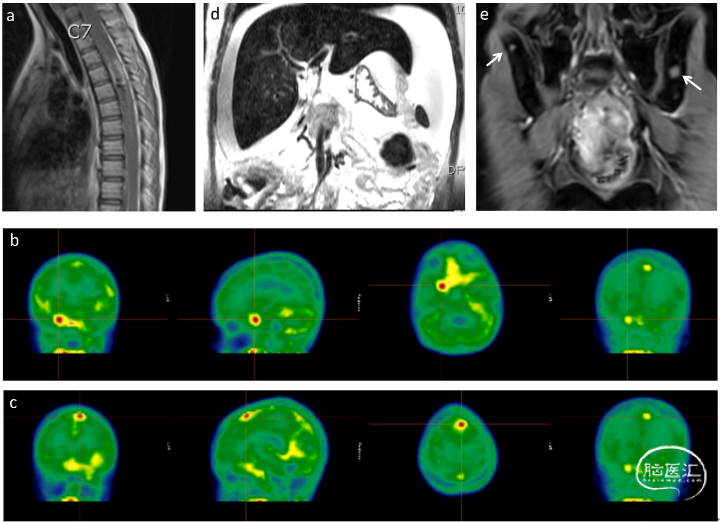

本文介绍一例儿童患者因Dandy-Walker 综合症接受手术治疗,初步诊断是毛细胞星形细胞瘤伴软脑膜转移,根据SIOP-LGG 2004 方案进行治疗,治疗期间MRI显示部分反应,直至85周没有进展。停止治疗后8个月影像学显示疾病进展,同时伴有脑膜转移。活检样本免疫组化结果显示:GFAP、P53、ATRX、S100、突触素等表达阳性,Ki67为80%-90%。同时检出有1p36.3拷贝数缺失和KIAA1549-BRAF融合,但没有检出19q3.3拷贝数缺失,NGS检测结果未发现其他基因变异。肿瘤的甲基化阵列分析结果显示DLGNT MC-2亚型。在接受长春碱单药治疗后出现疾病进展,后采用放射治疗,MRI显示部分反应并在治疗后7个月内疾病稳定。随后出现腹水等提示大网膜转移,同时出现髂骨和股骨病变,免疫组化结果显示MAP2、S100和突触素阳性,提示DLGNT转移。再次进行药物治疗(长春碱、曲美替尼),治疗3周后死亡。

将原发肿瘤样本、腹水样本及PDCL样本进行甲基化测序,与173例参考样本的甲基化数据进行比对分析发现原发性肿瘤和PDCL样本和MC-2亚型聚集,但腹水样本没有和MC-2亚型聚集,这可能是由于样本微环境导致的。原发性肿瘤具有 9p 拷贝数缺失,但没有局灶性CDKN2A/B纯合缺失。在腹水样本和PDCL样本中出现局灶性CDKN2A/B纯合缺失。